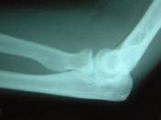

この写真は、整復後の写真です。傾斜した転移は十分に正常位置に整復されていることが確認されています。この写真は、8週目(58日目)のレントゲン写真です。骨折部位は治癒と判断されました。